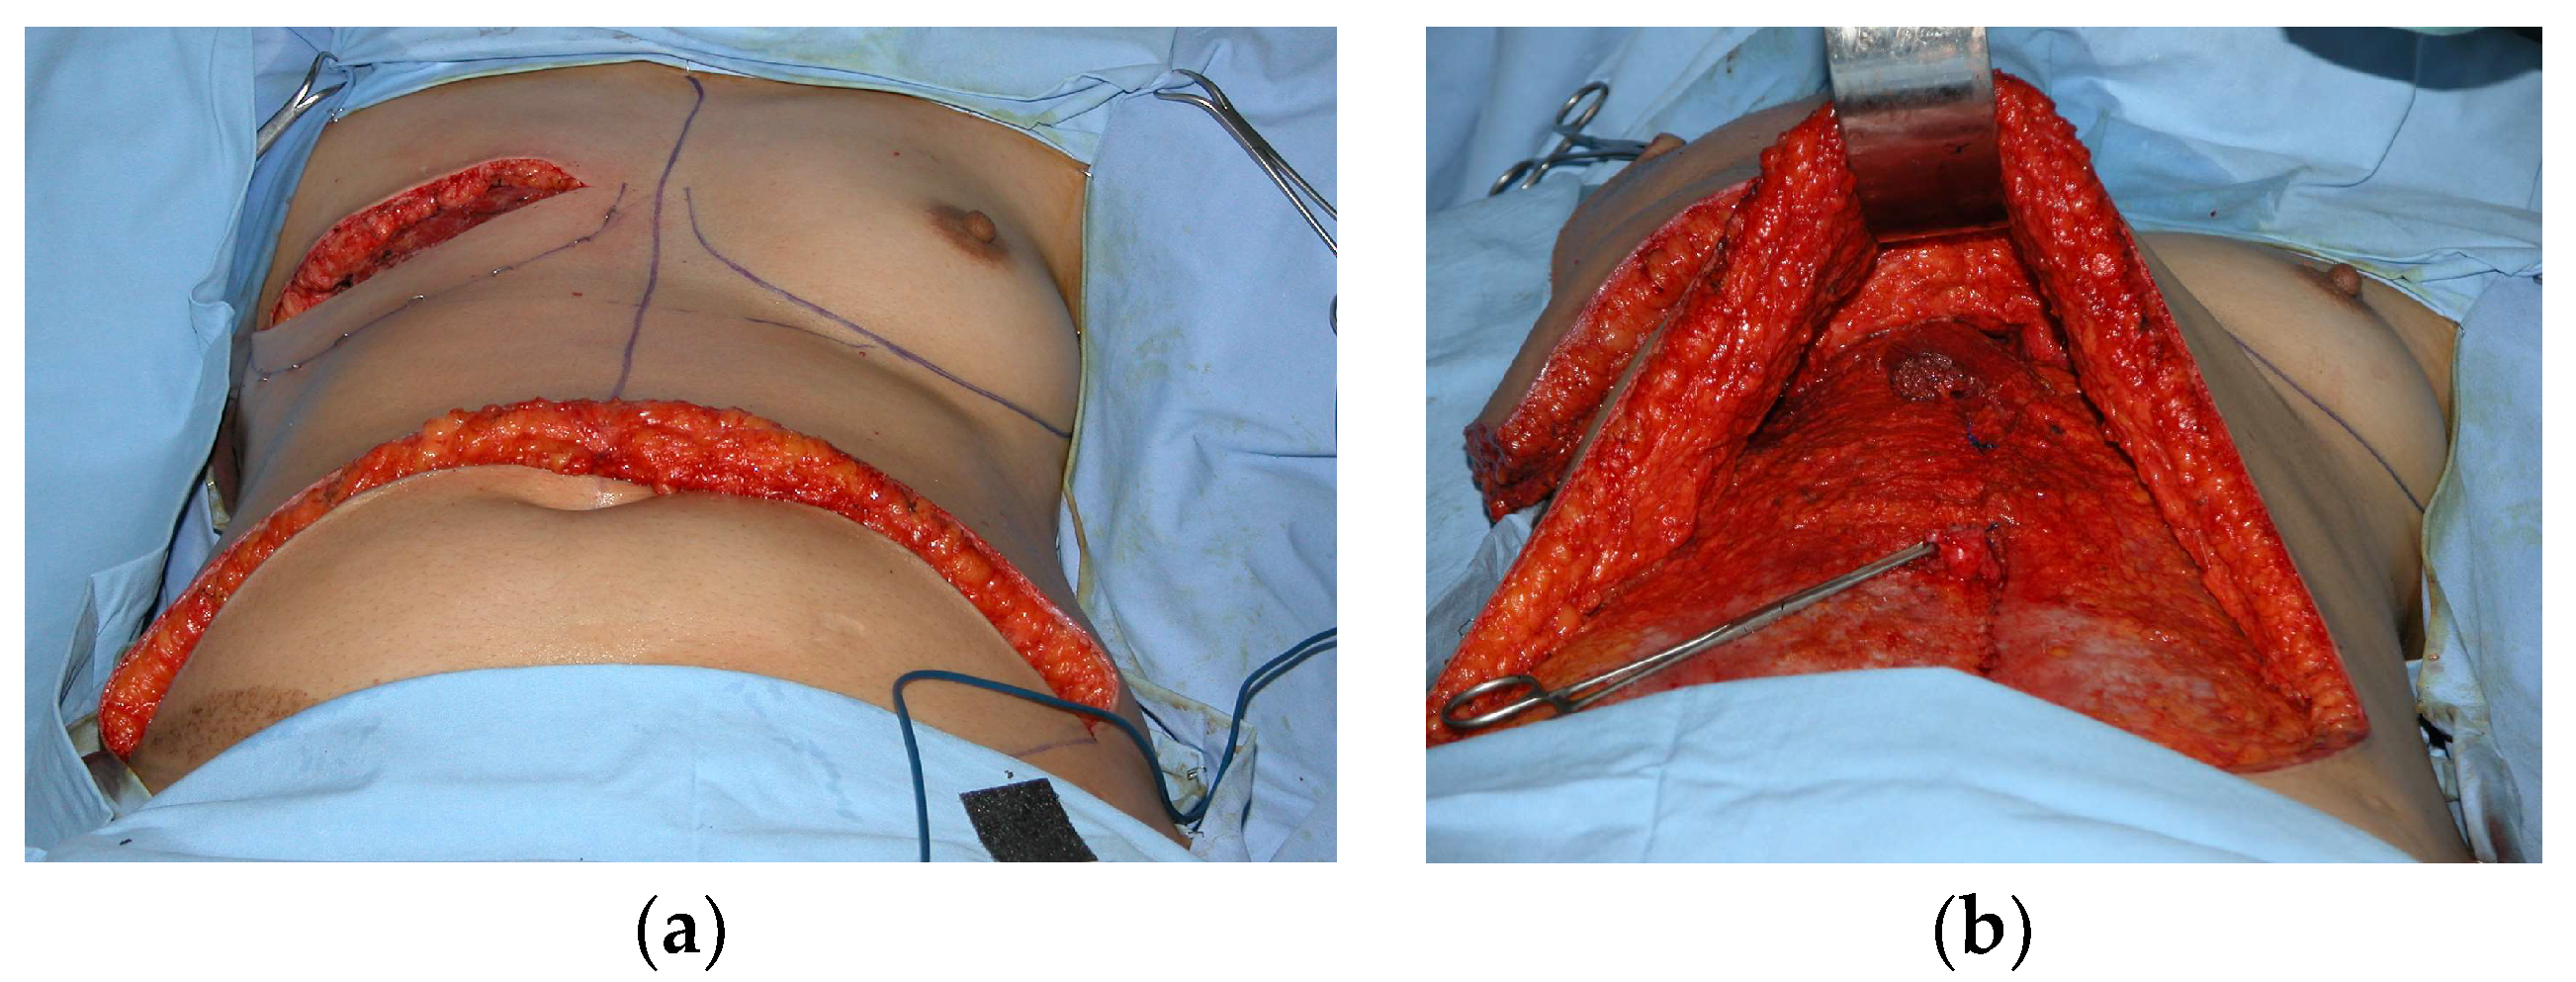

2.1.1. Transverse Abdominal Myocutaneous Pedicle (TRAM) Flap

2.1.2. Latissimus Dorsi Myocutaneous (LD) Flap